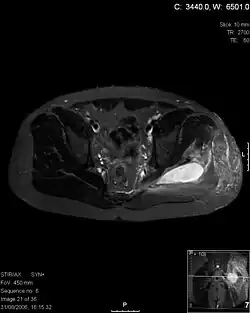

Axial T1 weighted fat suppressed post IV gadolinium contrast enhanced MRI image showing a mutliloculated bacterial abscess in the left gluteal muscle which grew Staphylococcus aureus (methicillin sensitive) thought to be due to tropical pyomyositis.